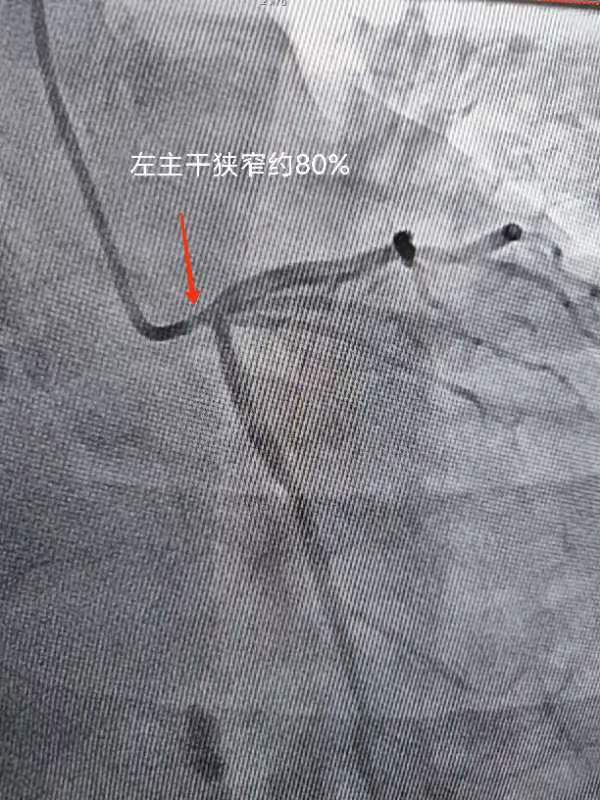

第二例患者主诉活动后气短,休息后好转,无胸痛、胸闷,运动耐量渐进性下降。经冠脉造影提示左主干严重病变,此类病变特点一旦发生急性冠脉事件,往往命悬一线,非常凶险,很多时候来不及到医院抢救。